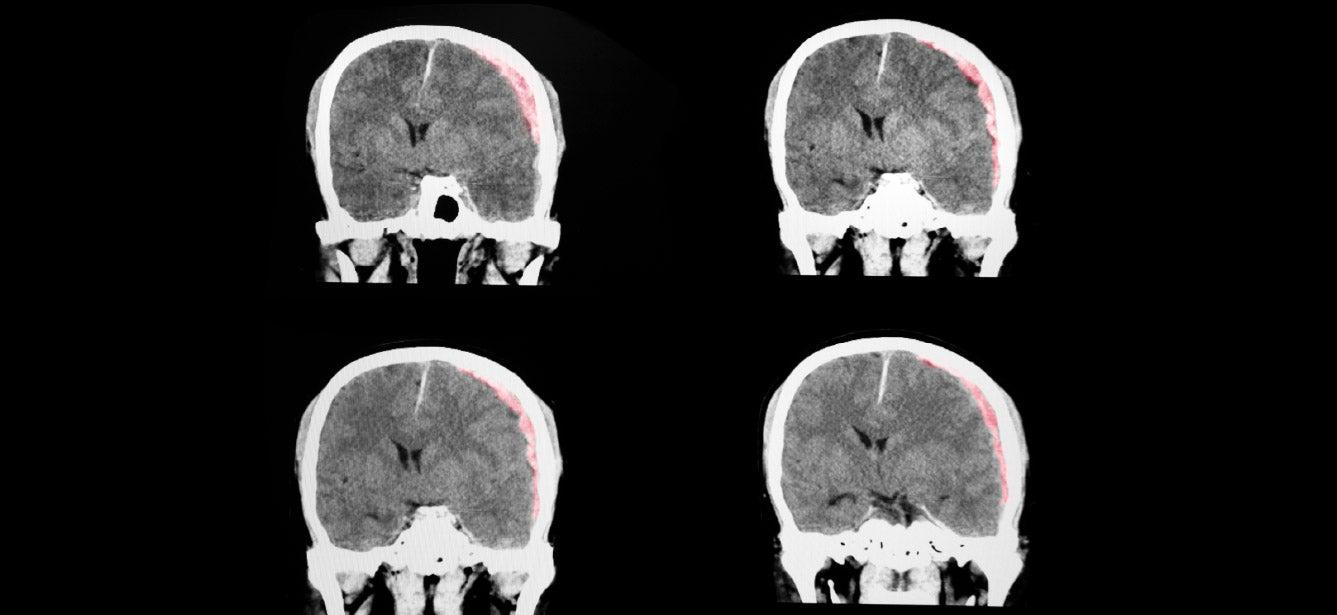

A traumatic brain injury is a type of injury that occurs when a sudden, external force or trauma affects the brain’s functioning. This force can result from a blow or jolt to the head (closed brain injury) or penetration of the skull (penetrating brain injury). "You may bump your head and it may hurt, but that doesn't necessarily mean that there's been a brain injury," said OAMHAD presenter Michael Hall, PhD, LCP, an Associate Professor in the Department of Physical Medicine and Rehabilitation at Virginia Commonwealth University. “There really needs to be disruption of how the brain is working."

TBIs are typically categorized as mild, moderate, or severe, based on the degree of impact on brain functioning. A brain injury may or may not involve a loss of consciousness immediately after the traumatic event. Symptoms of a mild TBI include: